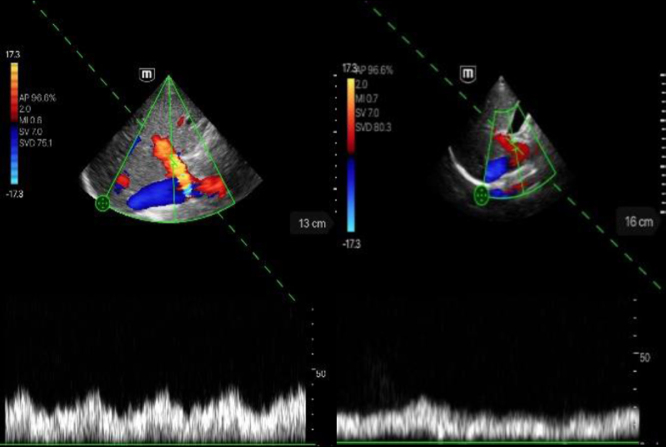

Methods: In this pilot study, the new ultrasound device TE Air from Mindray was used to examine the hepatic and renal vessels of healthy volunteers for first impressions. The probe has a sector transducer with a frequency range of 1.8-4.5 MHz. The B-mode and color-coded doppler sonography (CCDS) scanning methods were used. A high-end device from the same company (Resona 9, Mindray) was used as a reference. The results were evaluated using an image rating scale ranging from 0 to 5, with 0 indicating not assessable and 5 indicating without limitations.

Results: Altogether, 61 participants (n = 34 female [55.7%], n = 27 male [44.3%]), age range 18-83 years, mean age 37.9±16.5 years) could be adequately studied using TE AIR and the high-end device. With one exception, the image quality score for TE Air never fell below 3 and had a mean/median scored of 4.97/5.00 for the B-mode, 4.92/5.00 for the color flow (CF) mode, and 4.89/5.00 for the pulse wave (PW) mode of the hepatic vein, 4.90/5.00 for the portal vein, 4.11/4.00 for the hepatic artery, and 4.57/5.00 for the renal segmental artery. A significant difference in the assessment of flow measurement of the hepatic artery and renal segmental arteries was found between TE AIR and the high-end device.

Conclusions: TE Air represents a new dimension in point-of-care ultrasound via wireless handheld devices. Especially, its flow measurement ability offers a relevant advantage over other available handheld models. TE Air provides a formally sufficient image quality in terms of diagnostic significance.